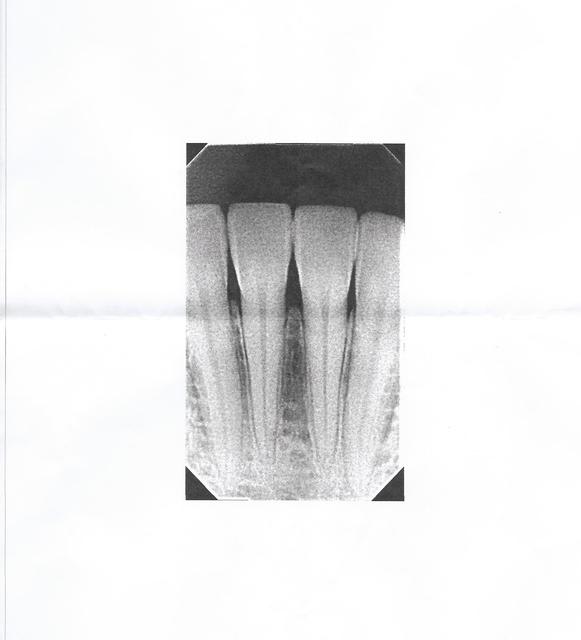

Ce post va sembler peut-être stupide mais je ne voudrais pas passer à côté de quelque chose... Il s'agit d'une amie, la trentaine, en bonne santé, non fumeuse, qui s'est vu prescrire par un confrère antibio+anti inflammatoire+examen sanguin à la suite d'une rétro-alvéolaire au niveau des incisives mandibulaires lors d'un examen de routine. Je précise que la patiente n'a aucun symptôme (pas de douleur palpation percussion froid, pas de gonflement, rien).

Bref, le praticien lui a dit qu'elle n'avait plus d'os entre 31 et 41, sans qu'il comprenne pourquoi.

J'ai refais une rétro car elle souhaitait avoir mon avis et perso je ne vois absolument rien, à part un os effectivement moins dense entre 31 et 41 mais qui me semble tout à fait physiologique. Il y a un petit élargissement desmodontale au niveau de la 41 qui est à mon avis la consequence de la légère rotation de la dent mais pour moi mon amie peut dormir tranquille.

L'avis du premier praticien m'ayant mis le doute, qu'est ce que vous en pensez?